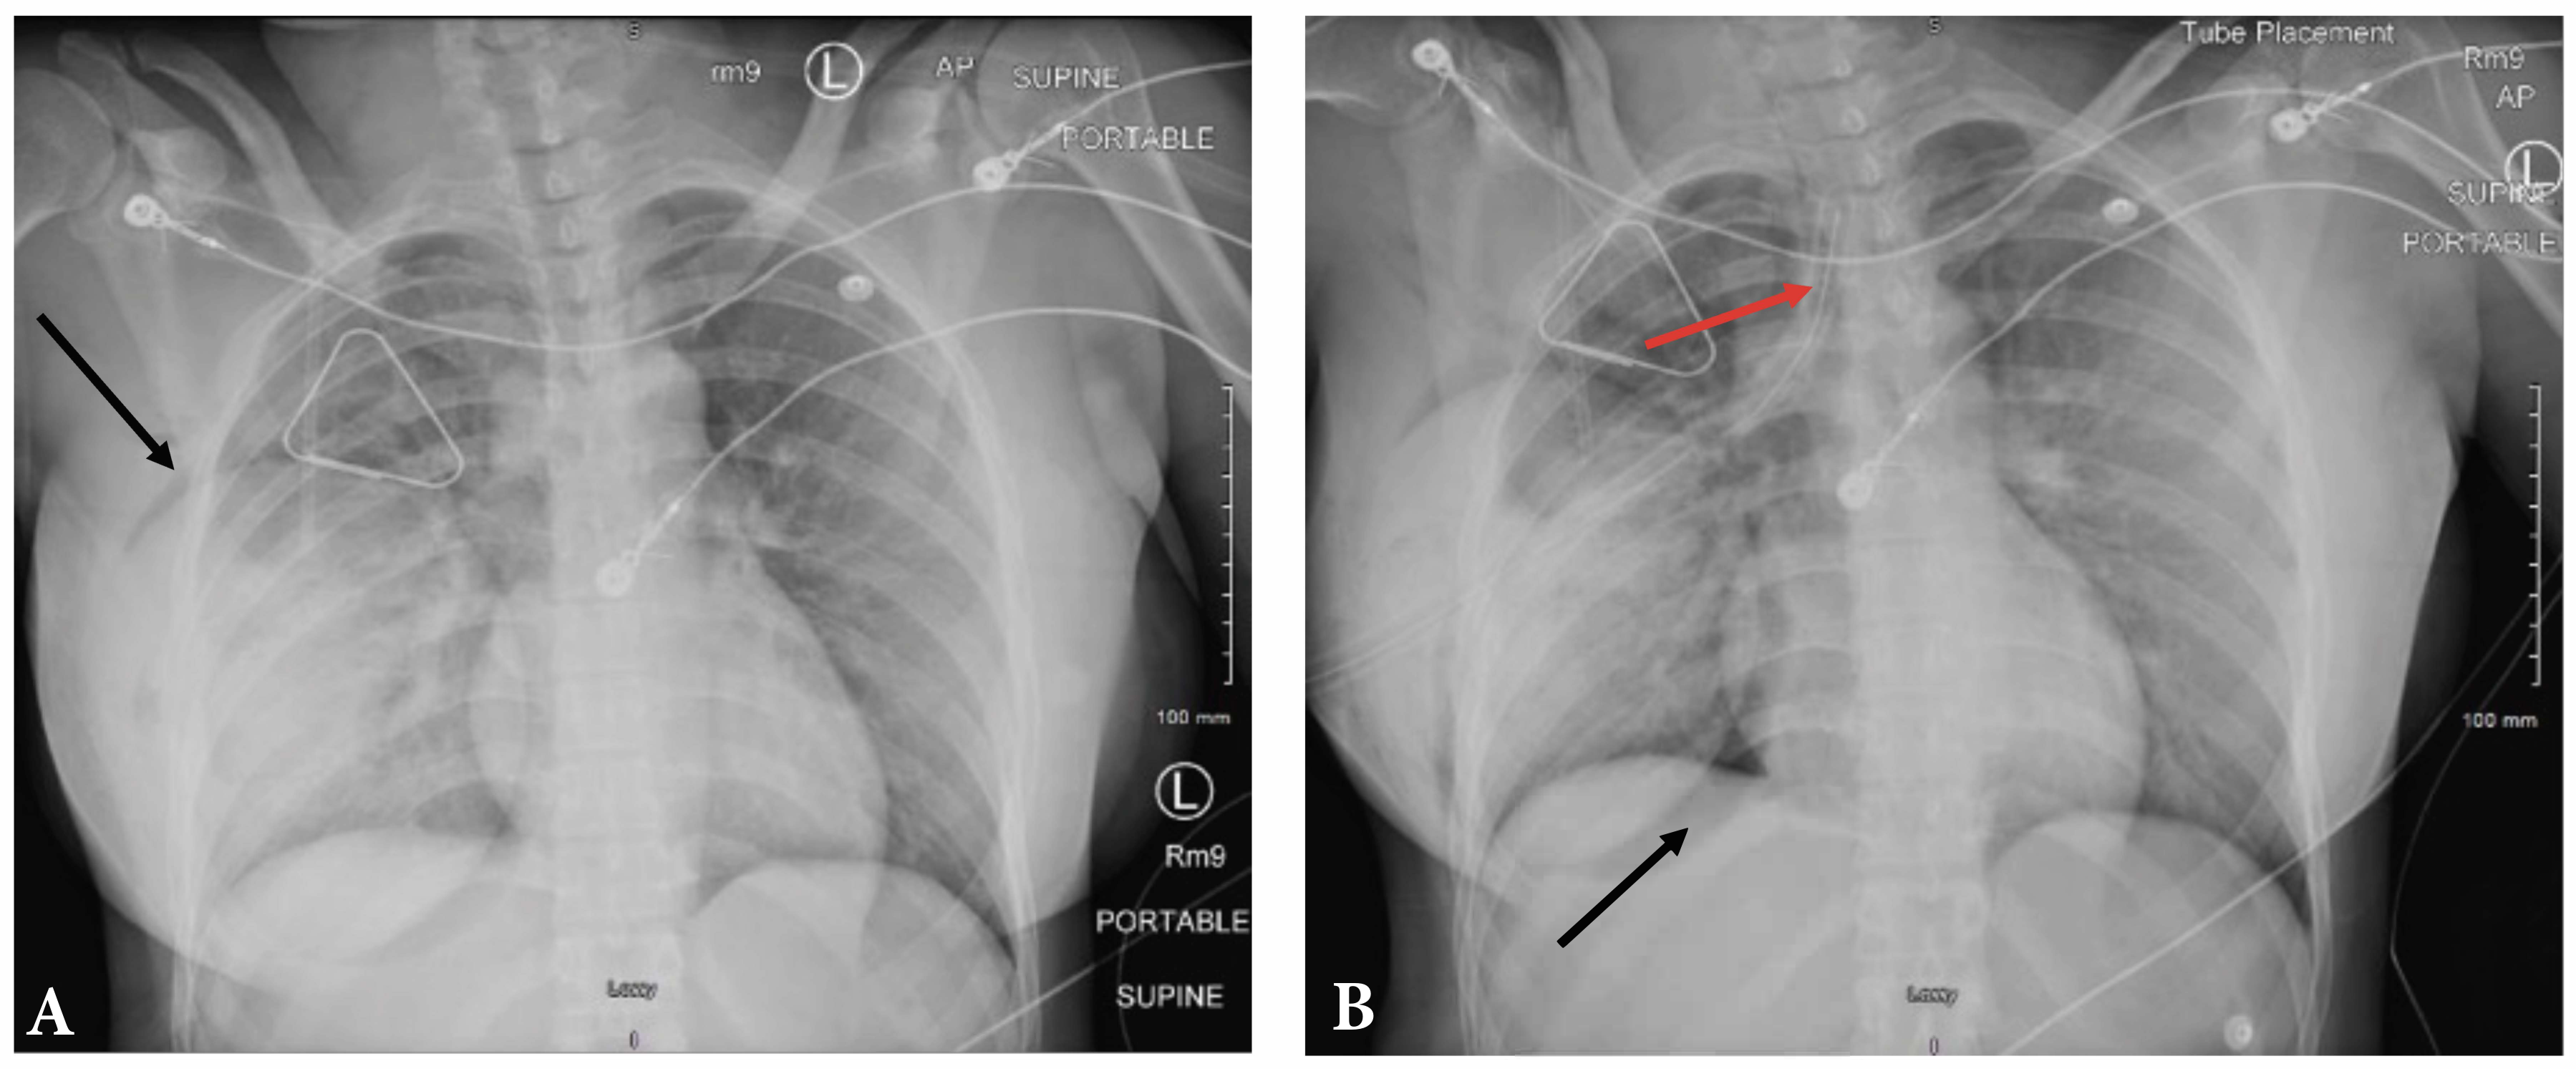

A 31-year-old woman who recently had a breast augmentation presented after sustaining a gunshot wound to the right chest. Ballistic wounds were noted on the anterior and lateral chest walls (Figure 1). Before arrival she underwent needle decompression, which was exchanged for a tube thoracostomy.

Chest radiographs showed an appropriately placed chest tube with re-expansion of the lung and air surrounding the implant (Figure 2). Computerized tomography revealed the ballistic trajectory, which grazed the right upper lobe of the lung, and demonstrated a small hemopneumothorax, air within and around the breast implant, and comminuted rib fractures (Figure 3A).